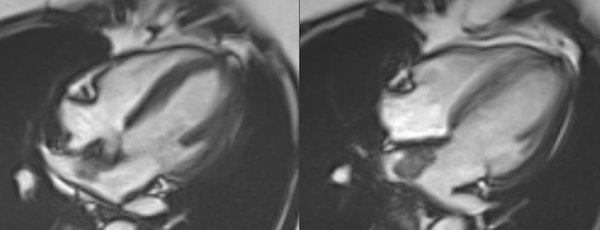

Not in Sync anymore..!

A common clinical presentation of LBBB induced cardiomyopathy is described in this post. It is always dilemma that if LBBB is cause or effect of dilated cardiomyopathy. However CMR can help in differentiating it from other causes and also in predicting response to device therapy. Utilise CMR to the fullest.